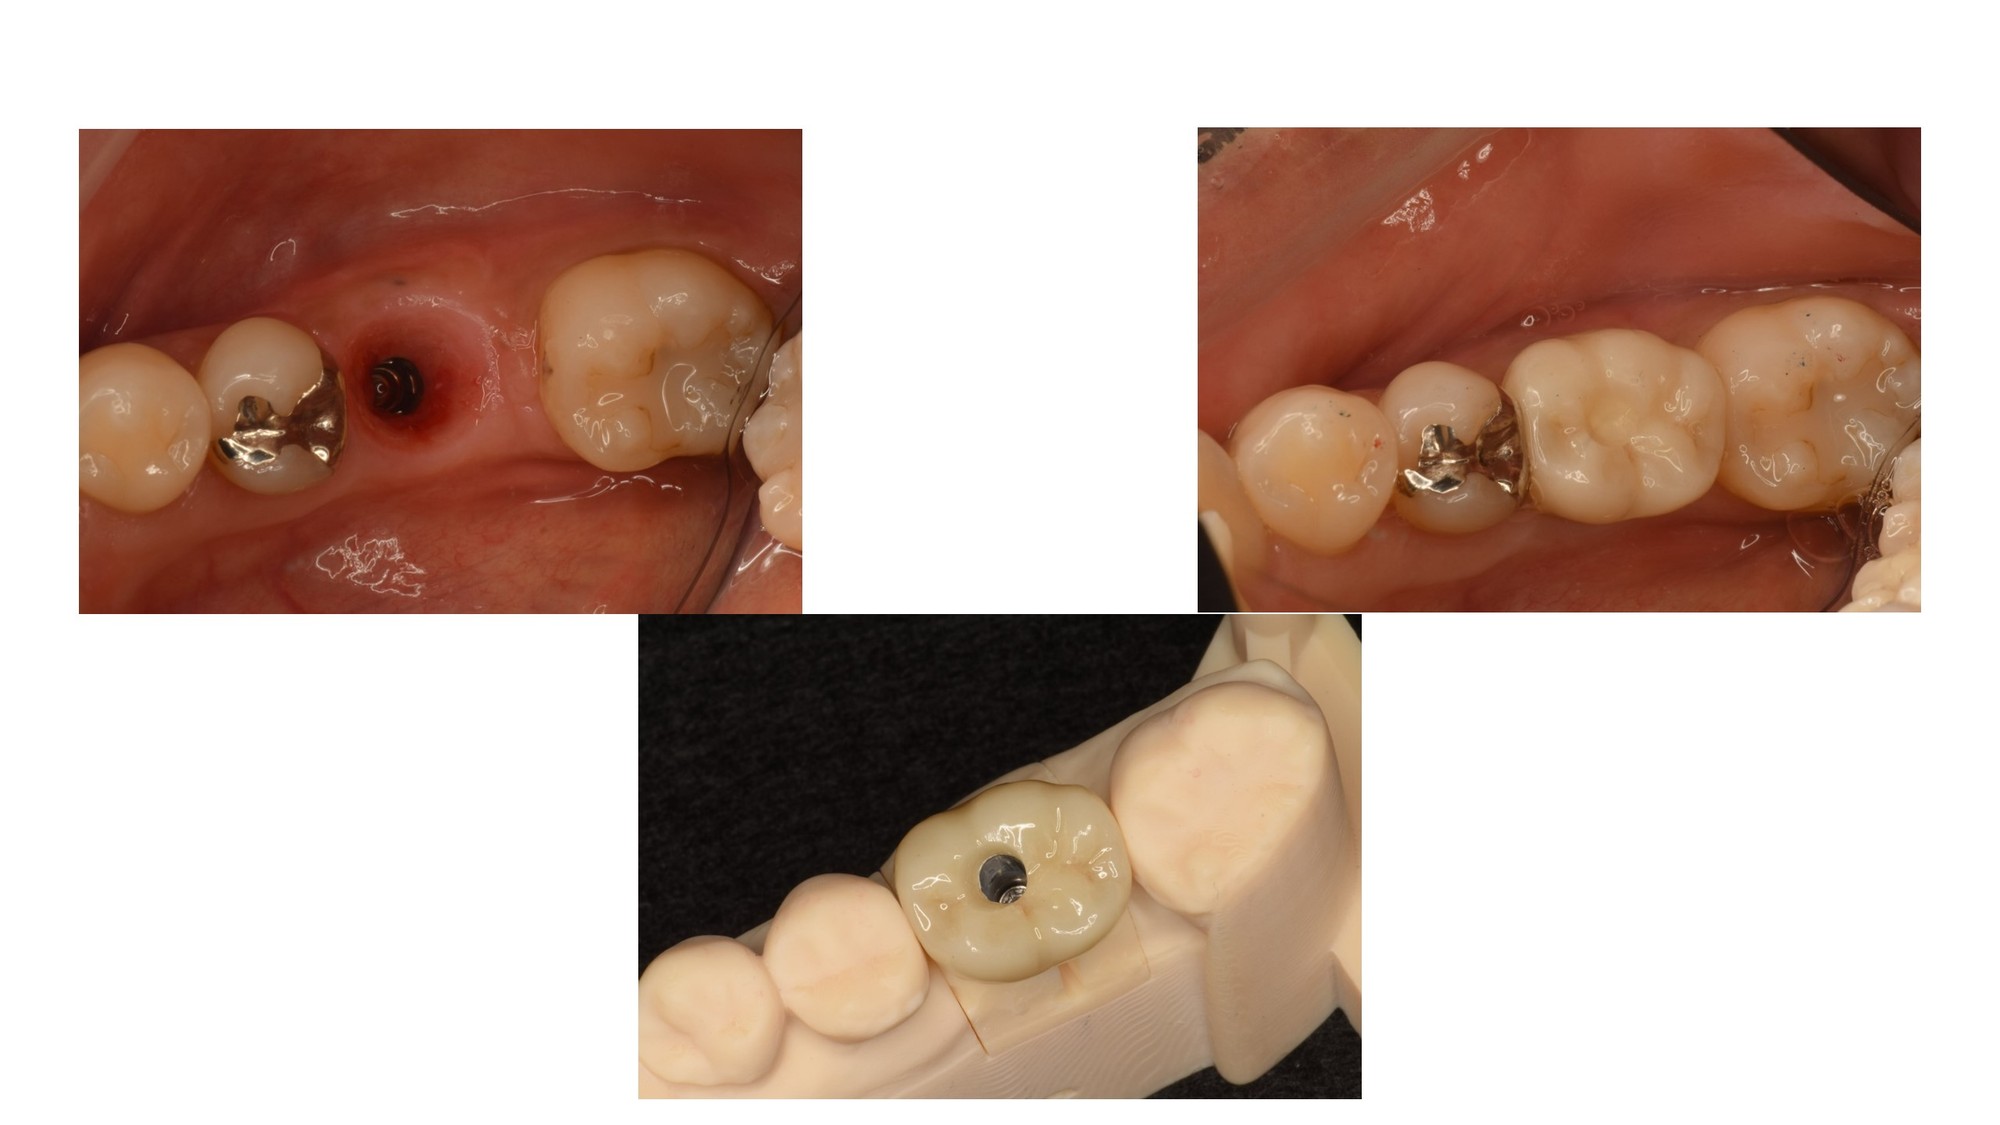

そして、ようやくここから、通常のインプラント処置がはじまります。

仮歯を経て、歯肉の成熟を待ち、最終補綴物を装着します。

スクリュー固定式のため、中央にアクセスホールが残ります。

治療期間 1年

費用 約60万円(うちGBR費用 約20万円)